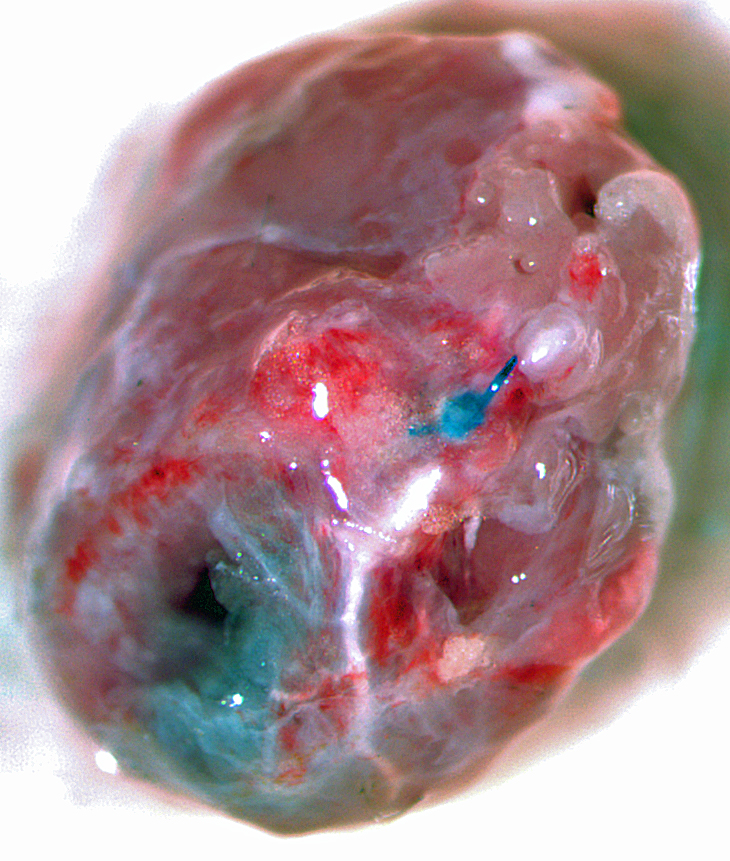

LAD Reperfusion Model: 30 Minute Ischemia with 2 Hour Reperfusion

Pictured: Cardiac Perfusion With Evans Blue Dye To Define Infarct zone.